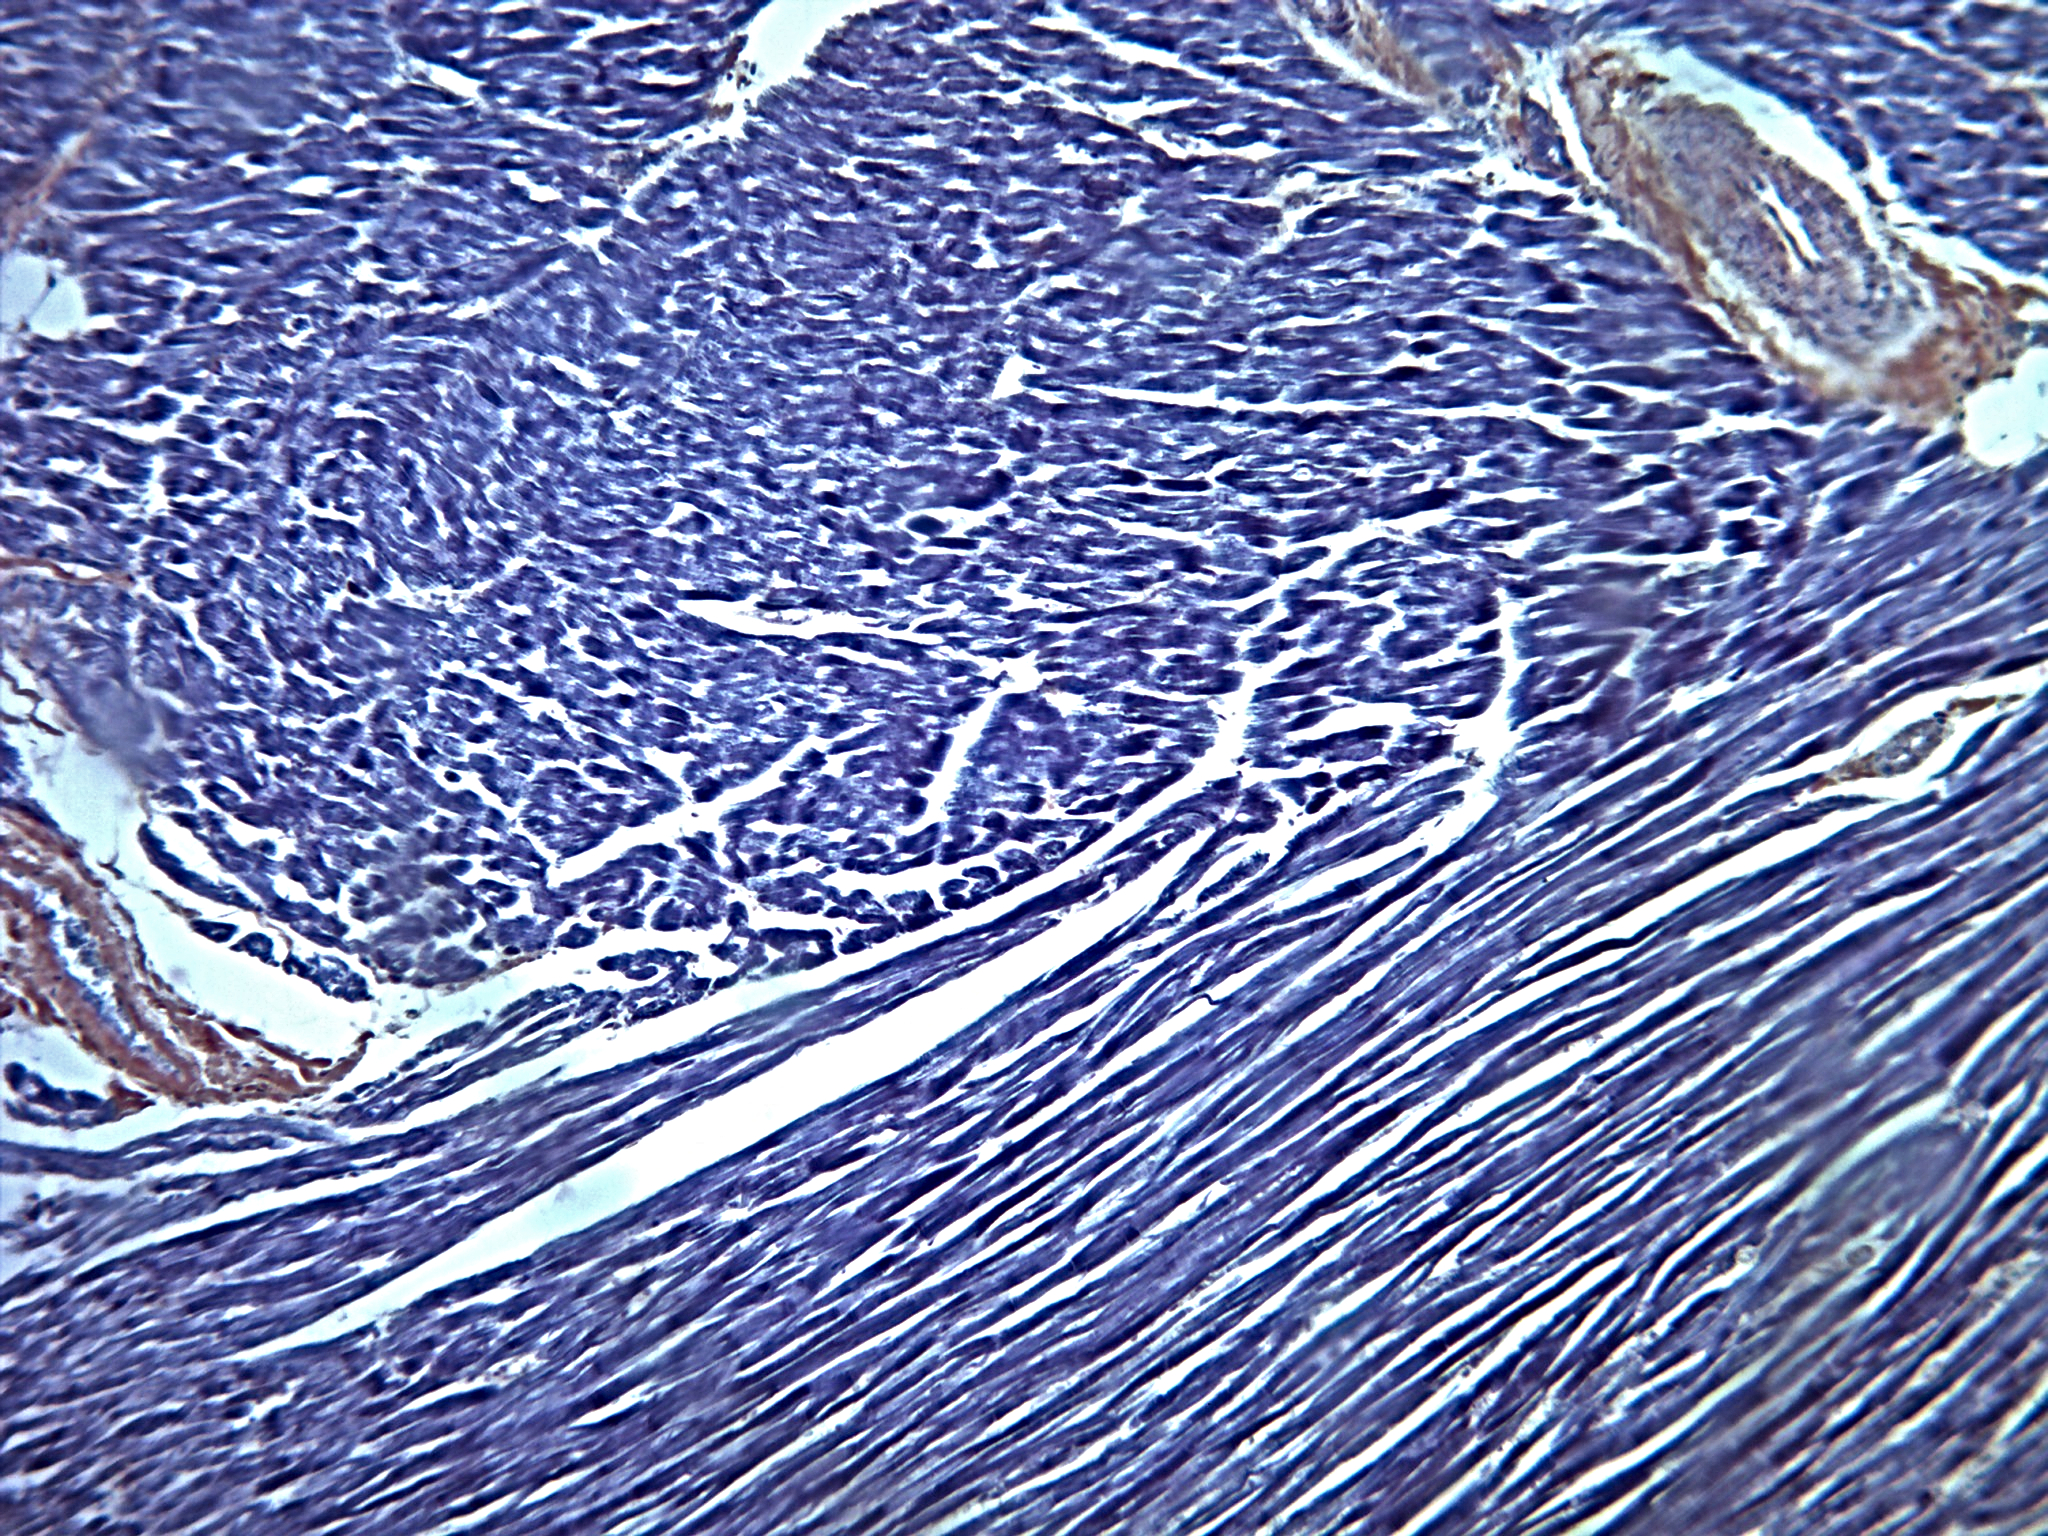

Sistema Circulatório